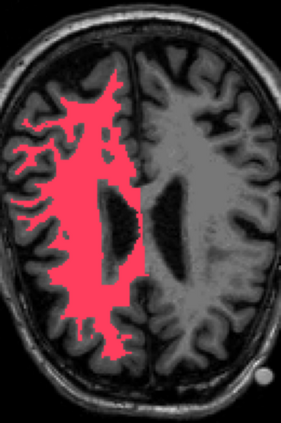

Deep neural networks for medical image reconstruction are traditionally trained using high-quality ground-truth images as training targets. Recent work onNoise2Noise (N2N) has shown the potential of using multiple noisy measurements of the same object as an alternative to having a ground truth. However, existing N2N-based methods cannot exploit information from various motion states, limiting their ability to learn on moving objects. This paper addresses this issue by proposing a novel motion-compensated deep image reconstruction (MoDIR) method that can use information from several unregistered and noisy measurements for training. MoDIR deals with object motion by including a deep registration module jointly trained with the deep reconstruction network without any ground-truth supervision. We validate MoDIR on both simulated and experimentally collected magnetic resonance imaging (MRI) data and show that it significantly improves imaging quality.